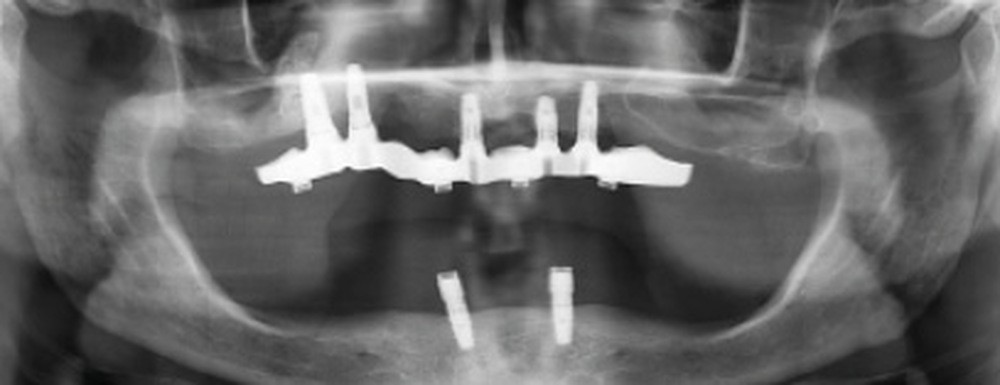

Une réhabilitation par PACSI maxillaire a été réalisée dix ans auparavant sur 5 implants en place de 13, 12, 21 et sur 24 et 26 (fig. 2a et b). Dans le cadre du plan de traitement initial, 6 implants avaient été indiqués. L’un d’entre eux, en position distale dans le secteur I, n’a jamais été ostéointégré. La patiente ne souhaitant plus de chirurgie, il avait donc été décidé de réaliser une prothèse sur 5 implants. La barre est directement connectée aux implants. À la mandibule, la patiente présente également une PACSI sur 2 implants associés à 2 piliers Locator®.